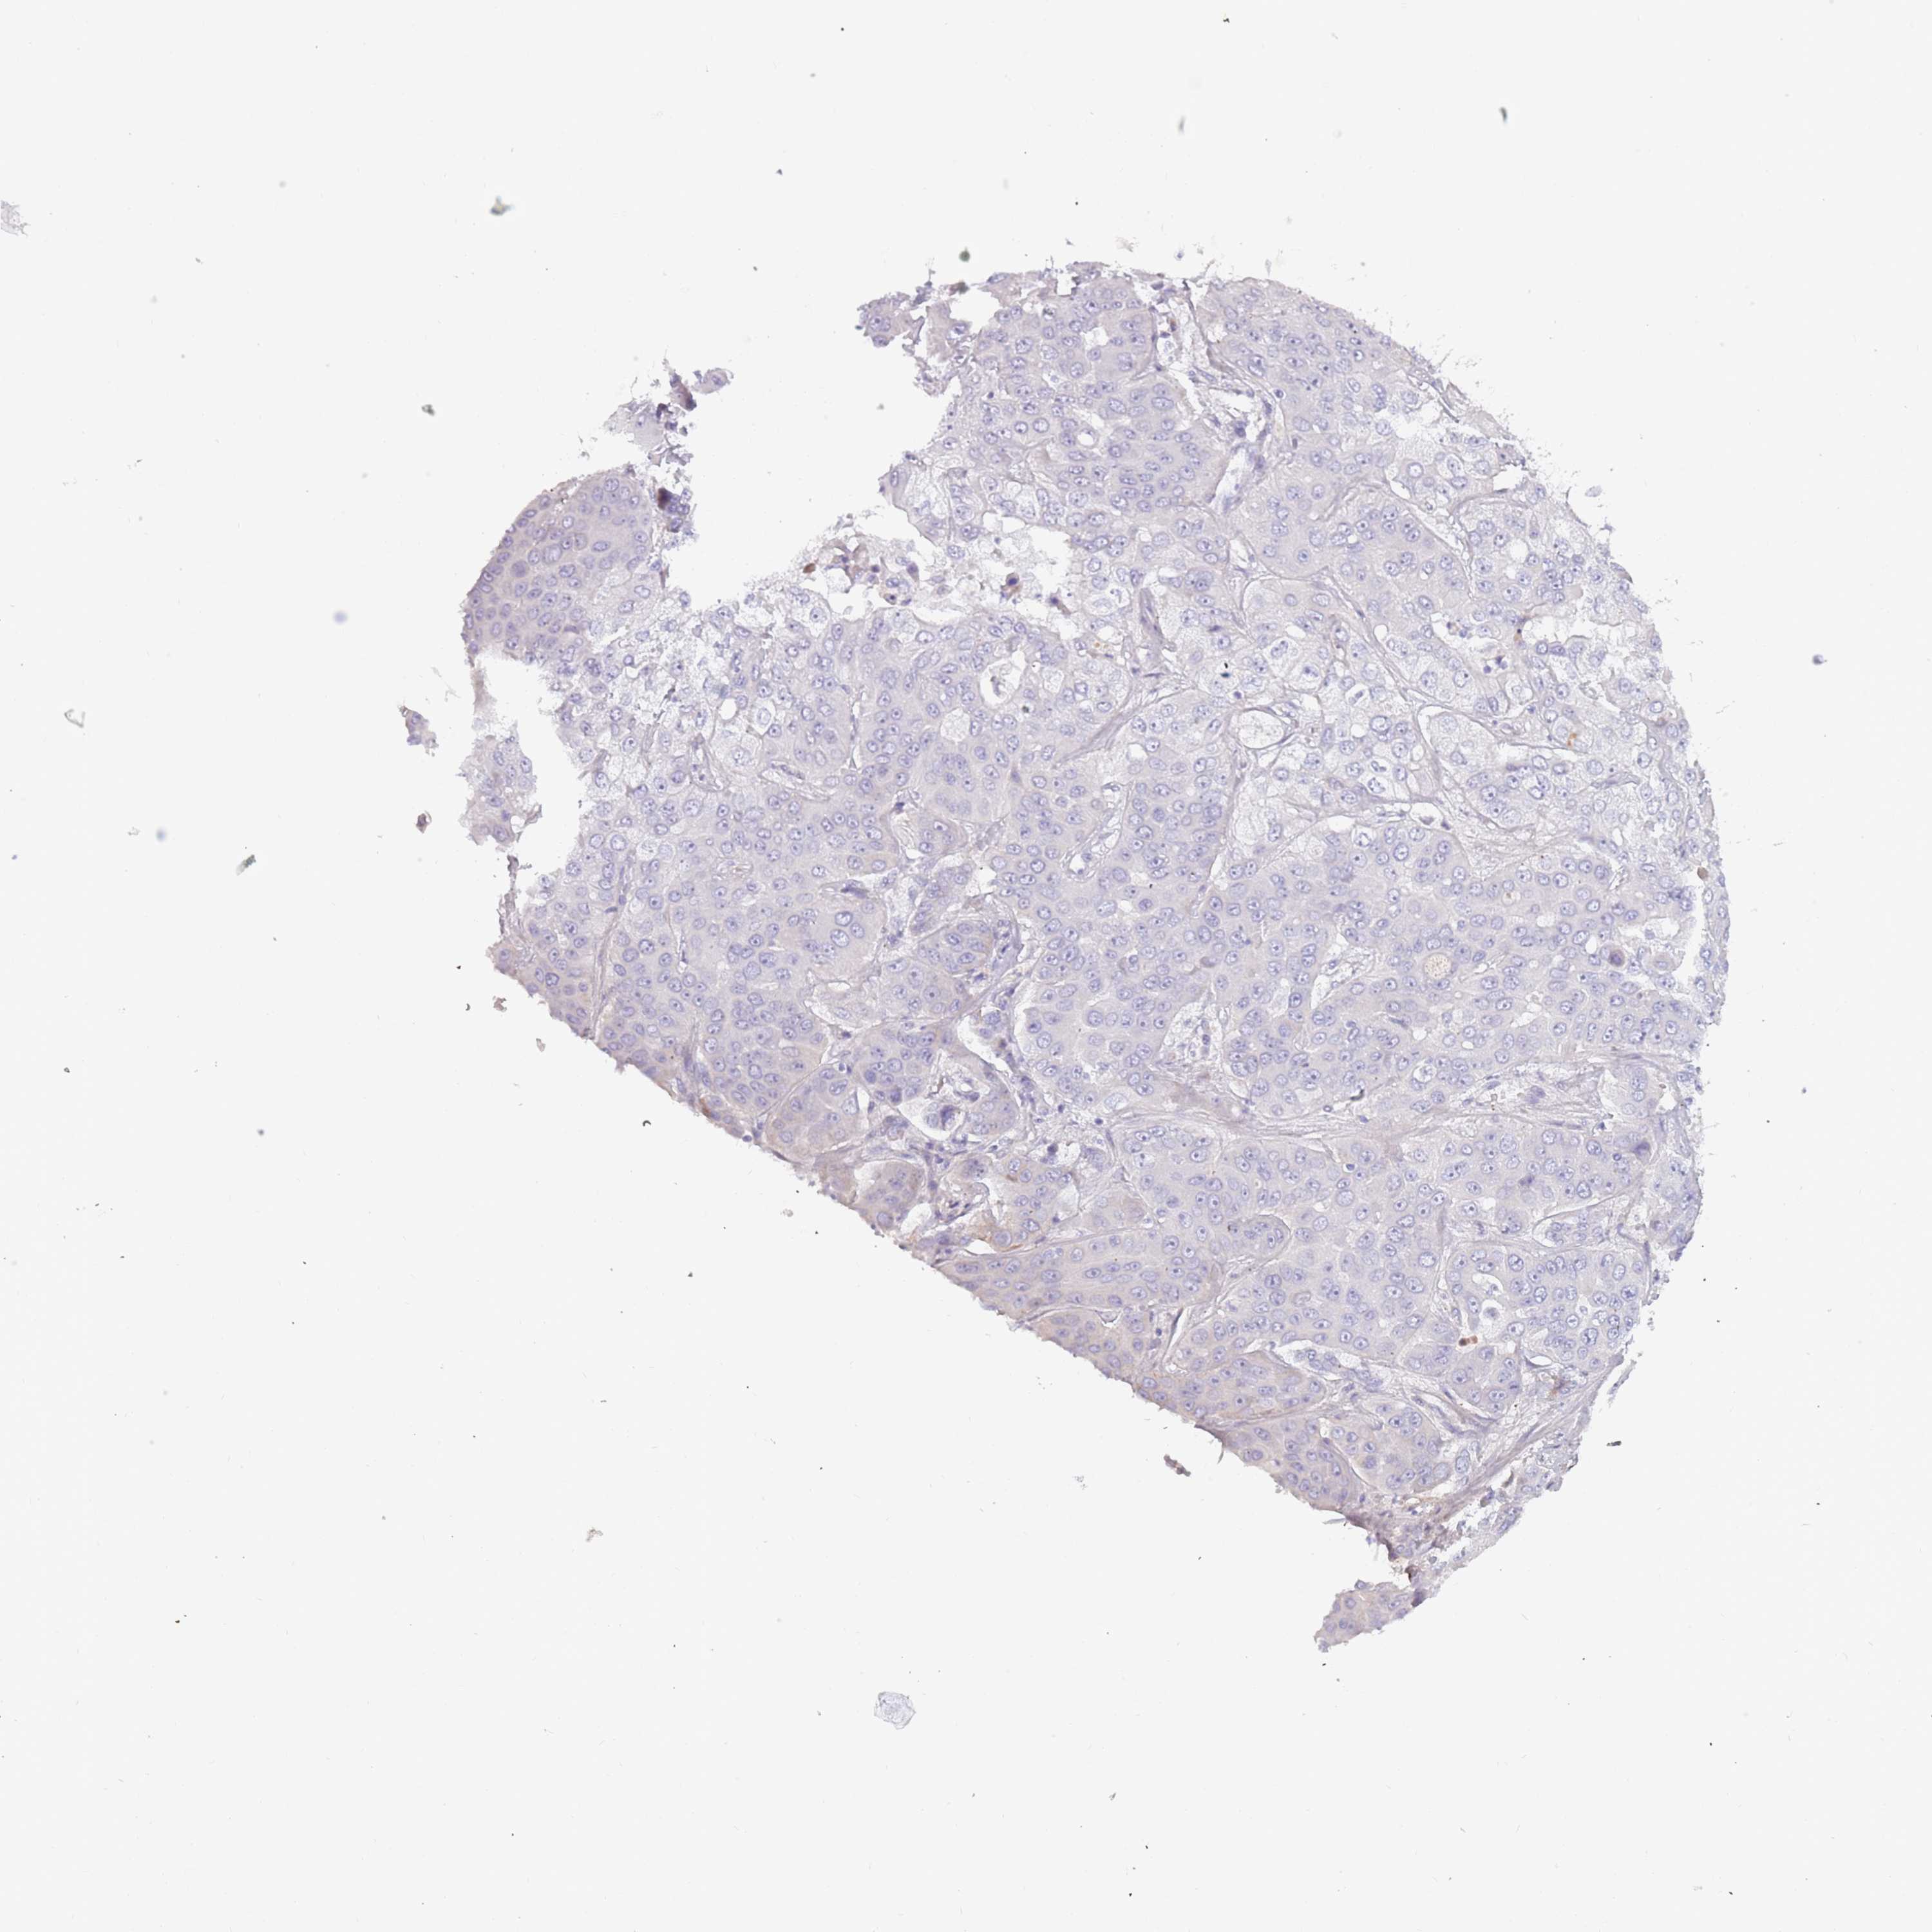

LIVER CANCER - Protein expressioni

A mouse-over function shows sample information and annotation data. Click on an image to view it in a full screen mode. Samples can be filtered based on level of antibody staining by selecting one or several of the following categories: high, medium, low and not detected. The assay and annotation is described here.

Note that samples used for immunohistochemistry by the Human Protein Atlas do not correspond to samples in the TCGA dataset.

Antibody stainingi

Antibody staining in the annotated cell types in the current human tissue is reported as not detected, low, medium, or high, based on conventional immunohistochemistry profiling in selected tissues. This score is based on the combination of the staining intensity and fraction of stained cells.

Each image is clickable and will lead to virtual microscopy that enables deeper exploration of all samples and also displays staining intensity scores, fraction scores and subcellular localization as well as patient and tissue information for each sample.

Antibody HPA047154

Staining

High

Medium

Low

Not detected

Intensity

Strong

Moderate

Weak

Negative

Quantity

>75%

75%-25%

<25%

None

Location

Nuclear

Cytoplasmic/membranous

Cytoplasmic/membranous,nuclear

Cholangiocarcinoma

Carcinoma, Hepatocellular, NOS